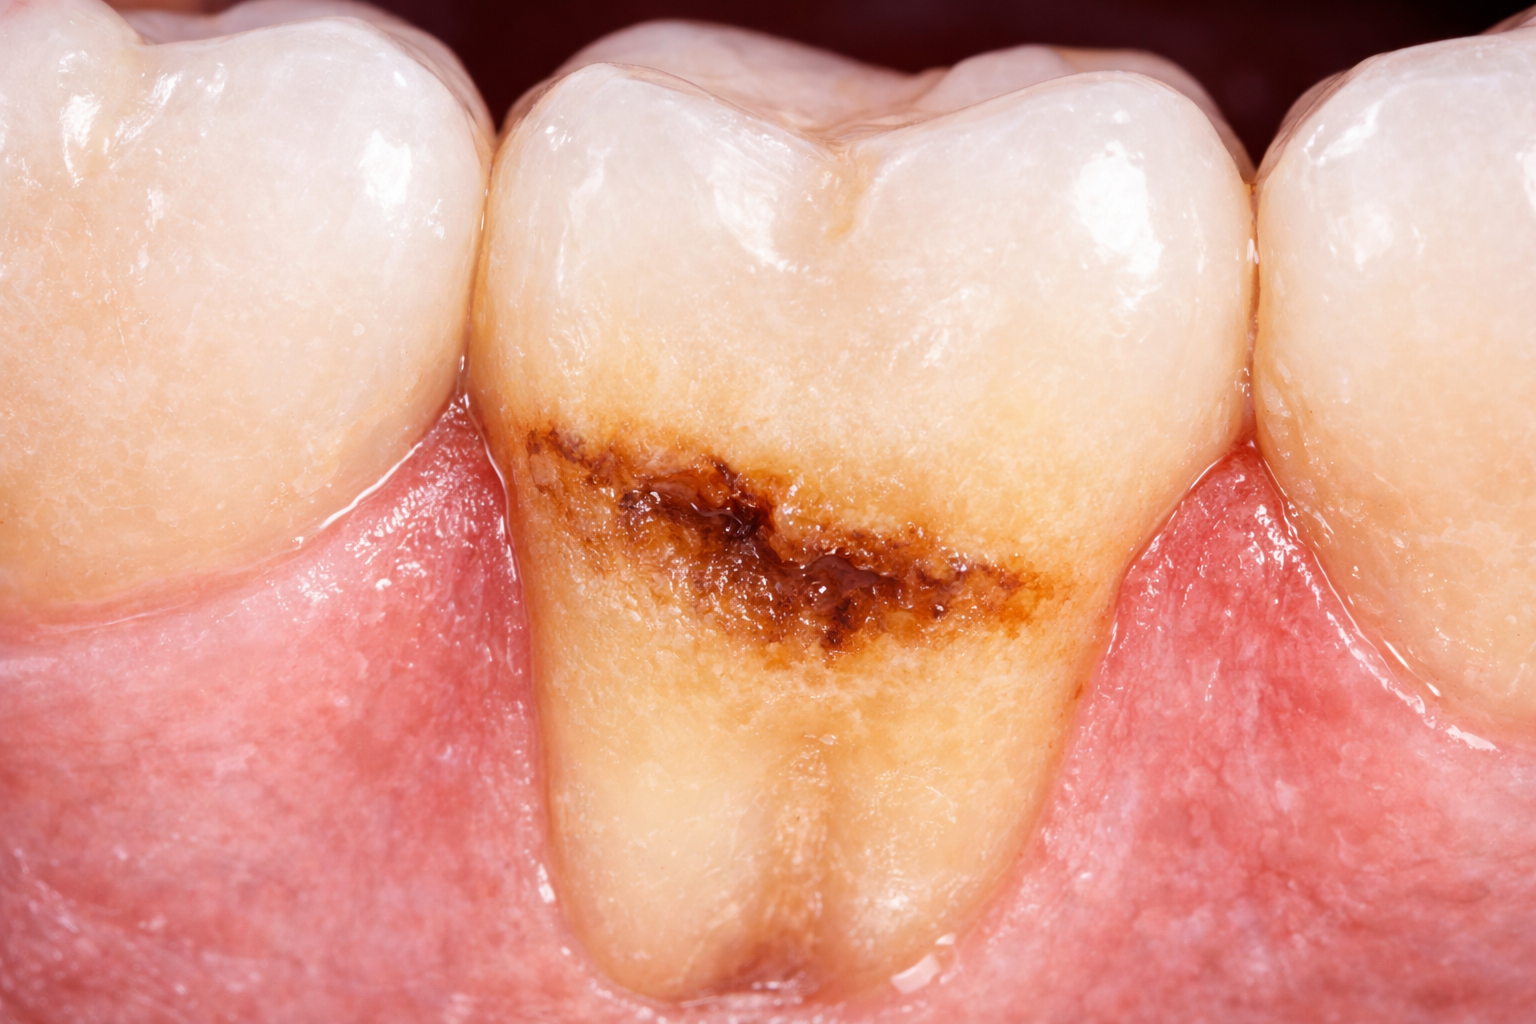

7) تسوس الجذور

يظهر هذا النوع على سطح الجذر عندما ينحسر اللثوي أو تنكشف الجذور. وهو أكثر شيوعاً عند كبار السن أو عند من لديهم انحسار لثوي. وبما أن سطح الجذر أقل مقاومة من المينا، فقد يتطور التسوس فيه بسرعة أكبر ويحتاج متابعة مبكرة لدى متخصص في أفضل عيادة أسنان بالكويت للتقويم واللثة.